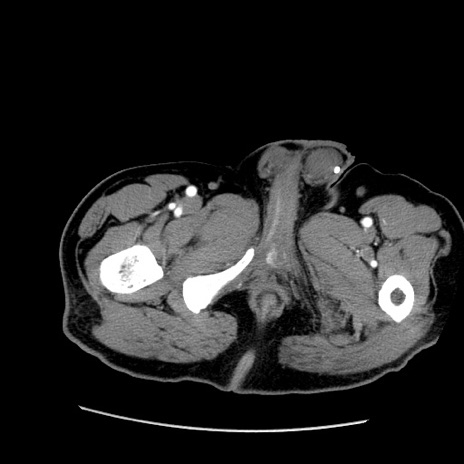

症例22(横断像)

【症例】50歳代男性

【主訴】腹痛

【現病歴】AVMからの被殻出血のため回復期リハ病棟入院中。 本日午後3時頃急に下腹部痛が出現した。

【既往歴】AVM、被殻出血、虫垂炎、高血圧

【身体所見】意識晴明、左半身不全麻痺、会話の理解は良好、36.5°C、腹部:膨隆、全体に板状硬、下腹部正中に圧痛点あり、反跳痛-、筋性防御不明、右下腹部にope scar

【データ】WBC 9400、CRP 0.06